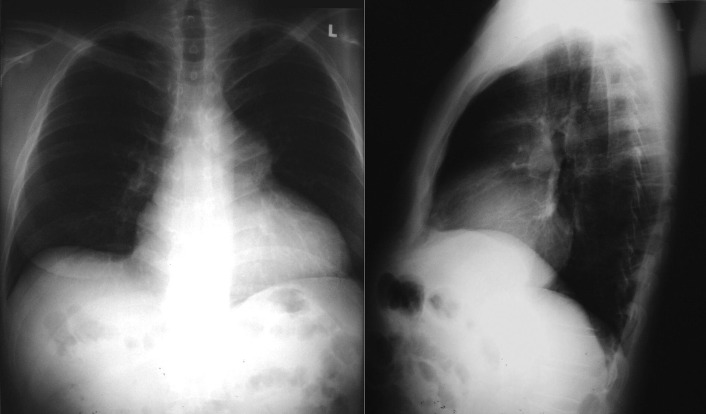

Posteroanterior and lateral projections: Valvular pulmonic stenosis. Note dilated main pulmonary artery seen on the frontal projection, and slight accentuation of the right atrial curvature. On the lateral projection, note the indirect sign of right ventricular dilation—increased apposition of the heart to the sternum, and dilation of the right main pulmonary artery, seen end-on.